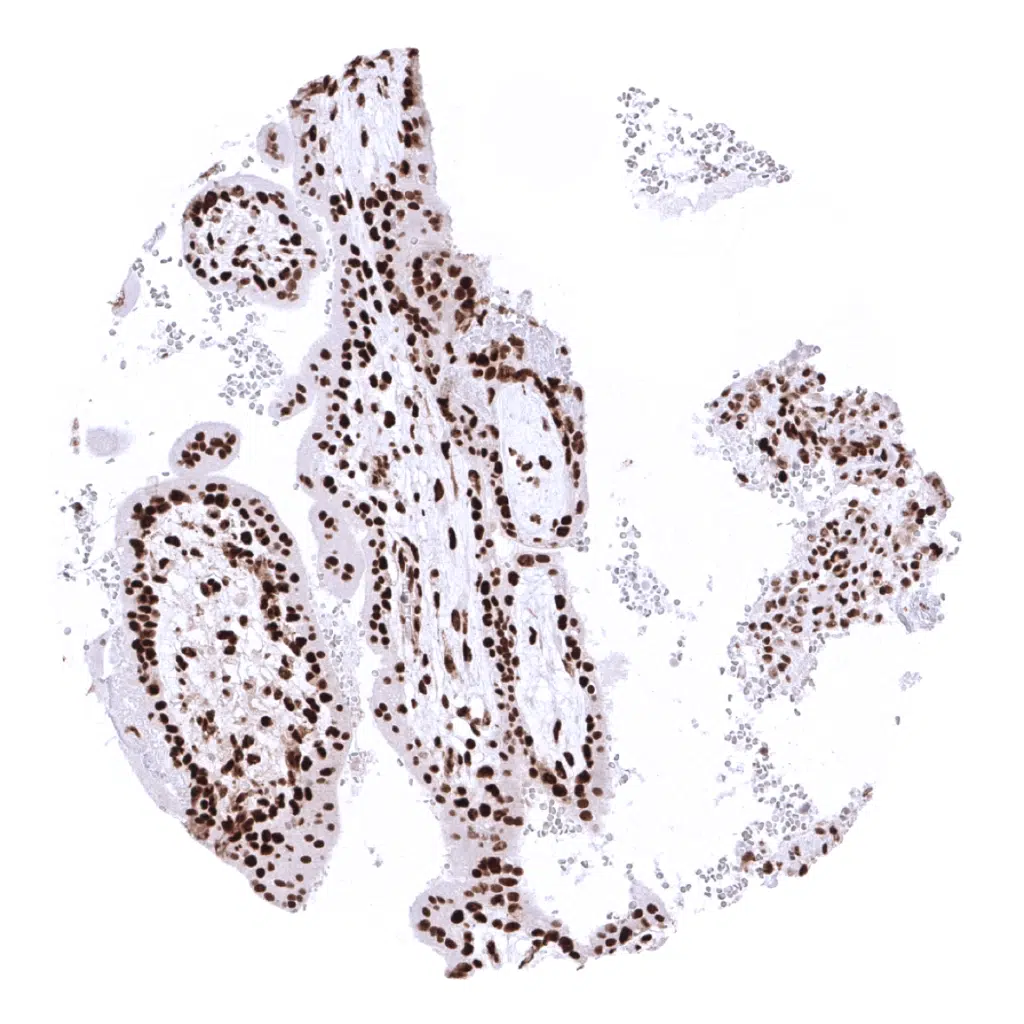

Placenta (amnion and chorion)